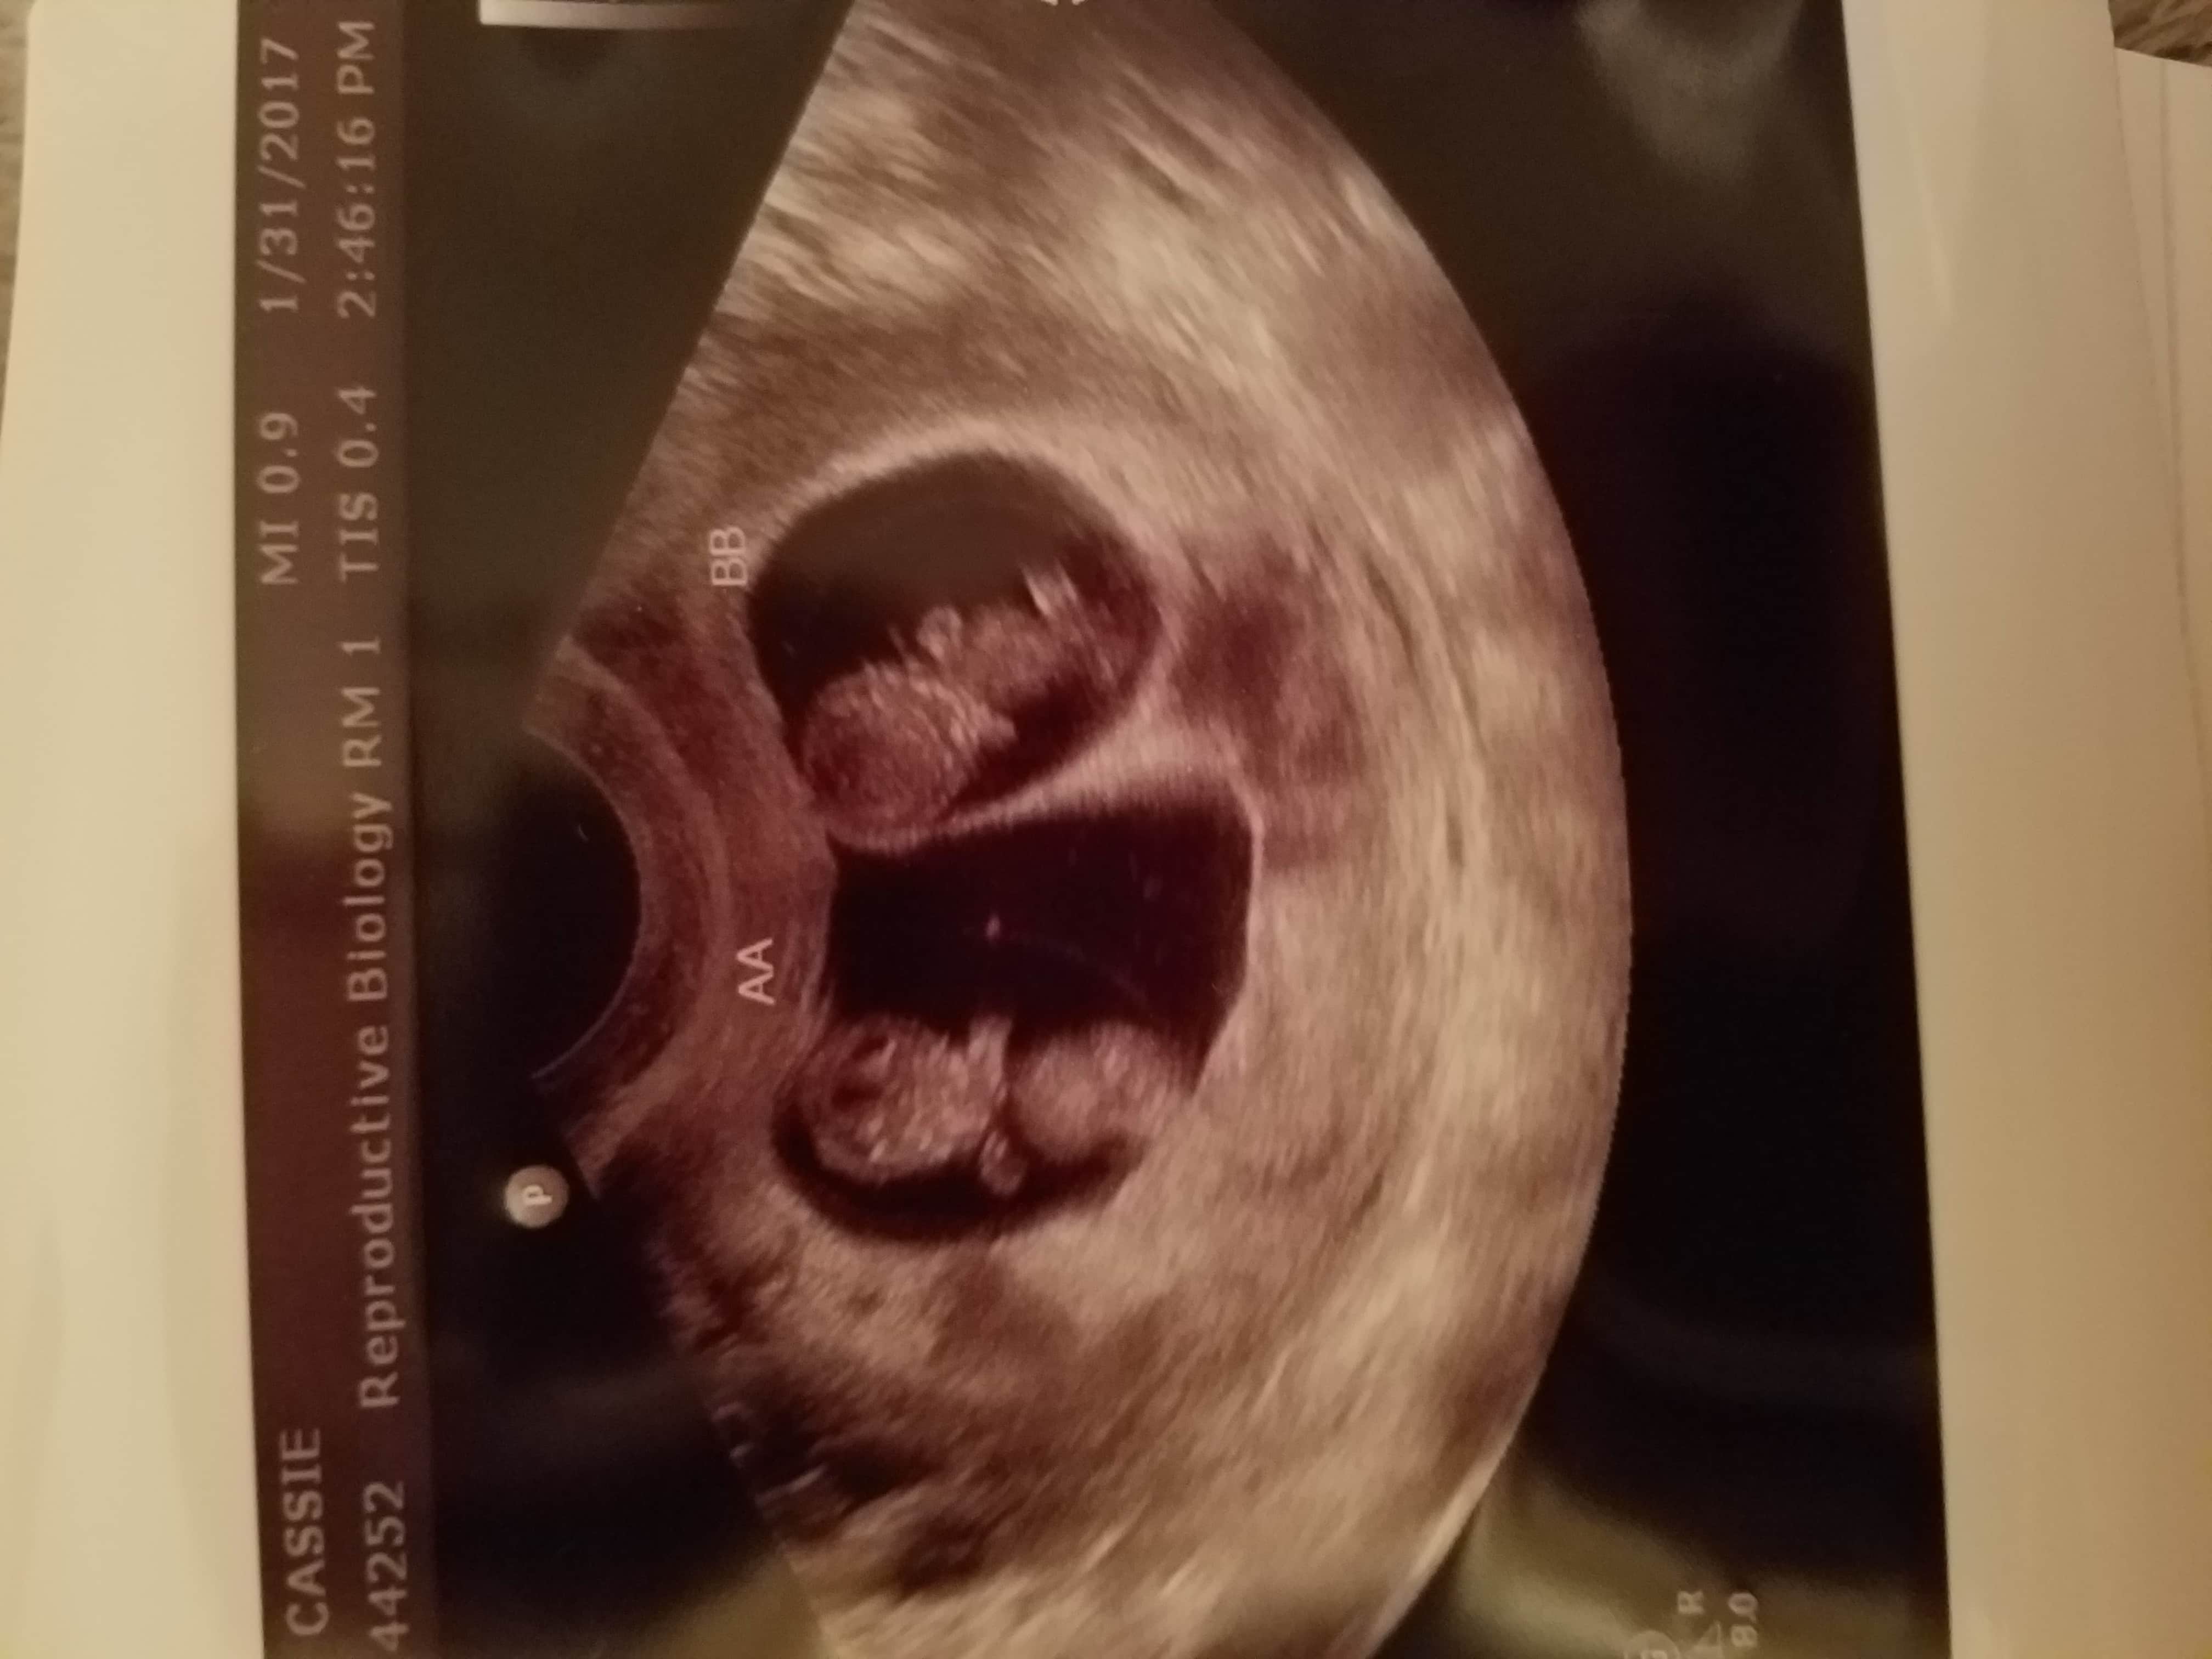

Ultrasound Photos of 9 Weeks Pregnant With Twins